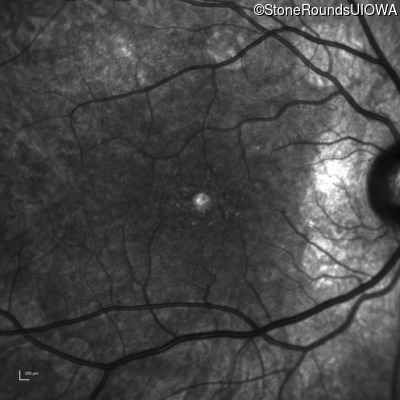

Infrared Fundus Photograph - Right - 20/20 -3

Exemplar